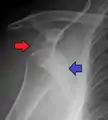

An anterior dislocation of the shoulder

Anterior dislocation of the right shoulder. AP X ray

In over 95% of shoulder dislocations, the humerus is displaced anteriorly.[7] In most of those, the head of the humerus comes to rest under the coracoid process, referred to as sub-coracoid dislocation. Sub-glenoid, subclavicular, and, very rarely, intrathoracic or retroperitoneal dislocations may also occur.[8]

Anterior dislocations are usually caused by a direct blow to, or fall on, an outstretched arm. The person typically holds his/her arm externally rotated and slightly abducted.